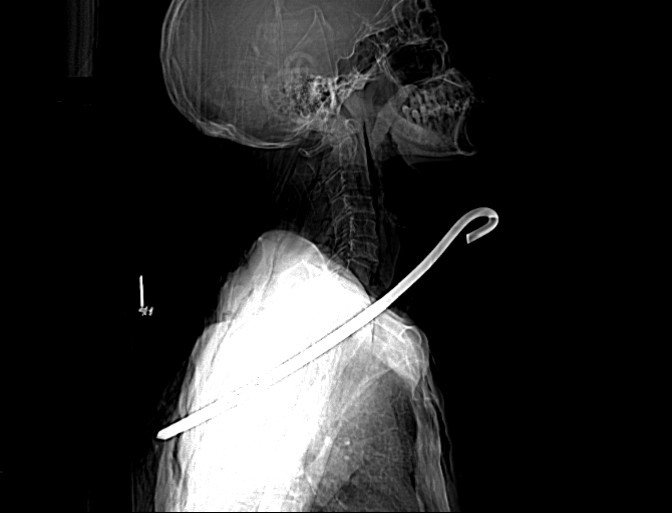

Kết quả chụp CT-Scan cho thấy, dị vật kim loại đường kính 0,8cm dài khoảng 30cm xuyên từ vùng cổ phải qua phổi phải và trung thất xuống vùng ngực bên trái; tổn thương rách thùy trên phổi phải, tràn khí màng phổi trái, tràn khí dưới da thành ngực và vùng cổ; gãy cung sau xương sườn số 5, 6 bên trái, gãy xương bả vai trái…